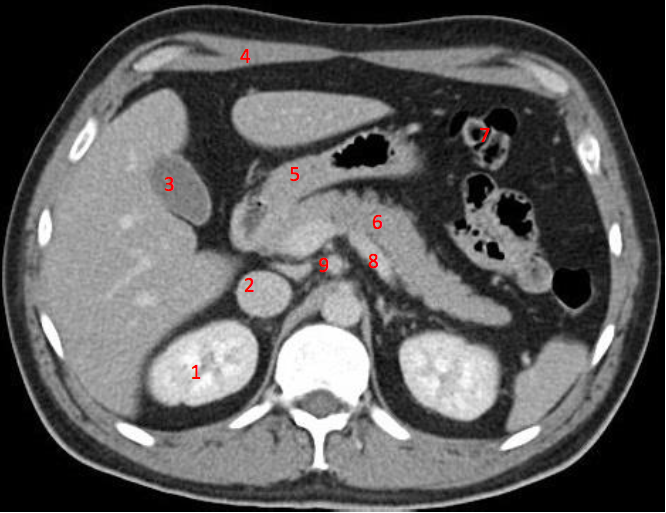

Number 3?

IVC

Number 1?

R Kidney

Gall bladder

Number 4?

Rectus abdominus

Head of pancreas

Number 7?

Bowel (probably large)

Number 6?

Stomach

Number 5?

Rt ureter

Descending colon

Number 9?

Superior mesenteric artery